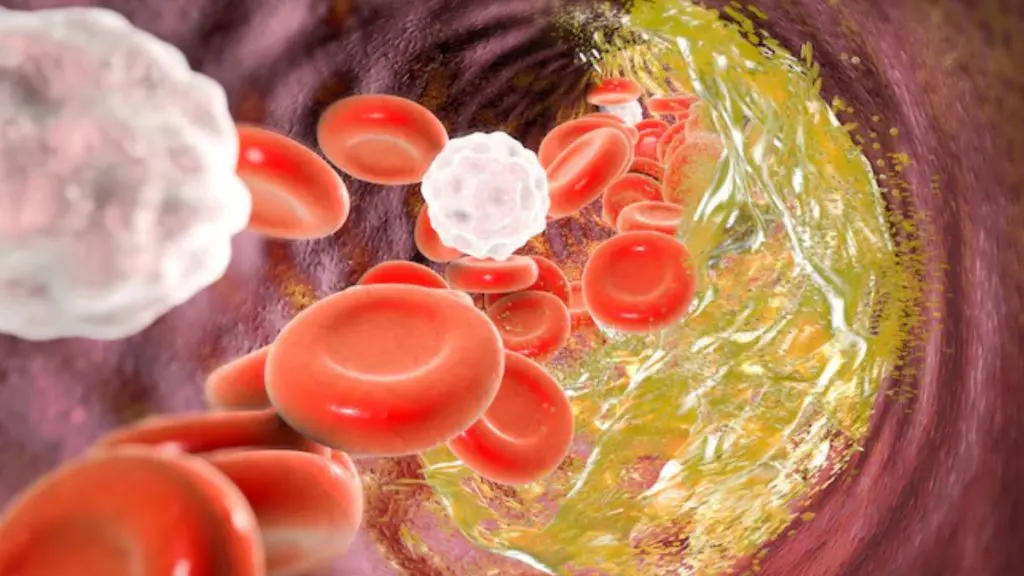

- બધા પ્રકારના કોલેસ્ટ્રોલ ખરાબ છે. ઘણા લોકો માને છે કે કોલેસ્ટ્રોલ ફક્ત શરીર માટે હાનિકારક છે જ્યારે આ અડધું સાચું છે. હકીકતમાં, ગુડ કોલેસ્ટ્રોલ ધમનીઓમાંથી ખરાબ કોલેસ્ટ્રોલને દૂર કરે છે અને જ્યારે તે હૃદયનું રક્ષણ કરે છે, ત્યારે ખરાબ કોલેસ્ટ્રોલ ધમનીઓમાં એકઠું થાય છે અને અવરોધનું કારણ બને છે.

- હાઈ કોલેસ્ટ્રોલના લક્ષણો સ્પષ્ટપણે દેખાય છે- આ એક મોટી ગેરસમજ છે. હાઈ કોલેસ્ટ્રોલ ઘણીવાર લક્ષણો વિના વિકસે છે અને સમસ્યા ગંભીર ન બને ત્યાં સુધી તે શોધી શકાતું નથી. તેથી, શ્રેષ્ઠ ઉકેલ એ છે કે સમયાંતરે બ્લડ ટેસ્ટ કરાવવા જરૂરી છે.

- મને એવું નથી લાગતું કે મને કોલેસ્ટ્રોલ વધારે છે. ઘણા લોકો એવું વિચારે છે કે થાક, માથાનો દુખાવો અથવા નબળાઈ તેમને કહી શકે છે કે તેમનું કોલેસ્ટ્રોલ કેટલું ઊંચું છે. જોકે, સત્ય એ છે કે શરીરને તેનો ખ્યાલ હોતો નથી. ઉચ્ચ કોલેસ્ટ્રોલનું ચોક્કસ નિદાન ફક્ત ટેસ્ટ દ્વારા જ થઈ શકે છે.